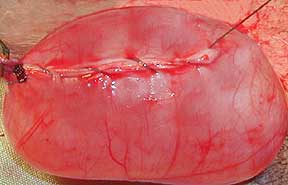

This is the appearance of a different dog that had a cancerous testicle, called a seminoma. It was not removed until later in life, so it had a chance to enlarge tremendously.